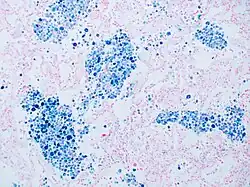

La coloration de Perls est une technique de coloration cytochimique de tissus utilisée en hématologie. Elle permet de mettre en évidence le fer fixé dans l'hémosidérine colorée en bleu par le bleu de Prusse[note 1] ; les noyaux sont mis en évidence par le rouge nucléaire.

La coloration de Perls est majoritairement employée pour diagnostiquer les syndromes myélodysplasiques par l'identification de sidéroblastes en couronnes sur les myélogrammes. Ces cellules sont des globules rouges immatures dont les granulations d'hémosidérine entourent le noyau[2].

La coloration peut également servir dans l'exploration des anémies pour évaluer la localisation et le métabolisme du fer[3],[4]. Les corps de Pappenheimer sont aussi visualisables[5],[6].